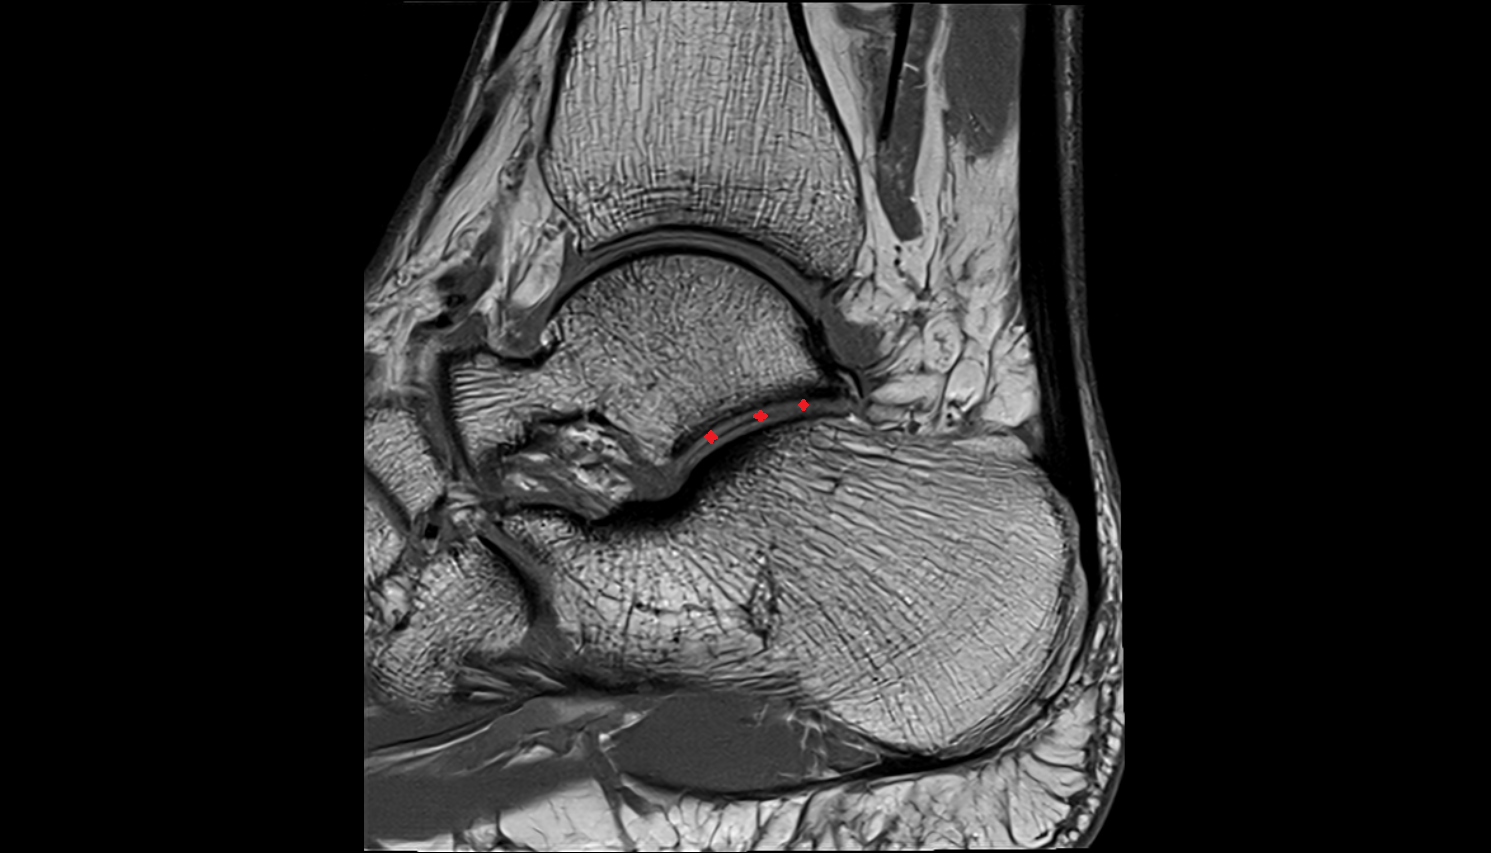

- Ankle joint

- Talus

- Calcaneus

- Achilles tendon

- Deltoid ligament complex